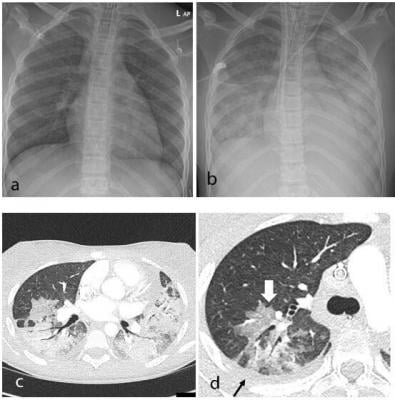

Children Free Full Text Multi System Inflammatory Syndrome In Children Mis C Following Sars Cov 2 Infection Review Of Clinical Presentation Hypothetical Pathogenesis And Proposed Management

Children Free Full Text Multi System Inflammatory Syndrome In Children Mis C Following Sars Cov 2 Infection Review Of Clinical Presentation Hypothetical Pathogenesis And Proposed Management from www.mdpi.com